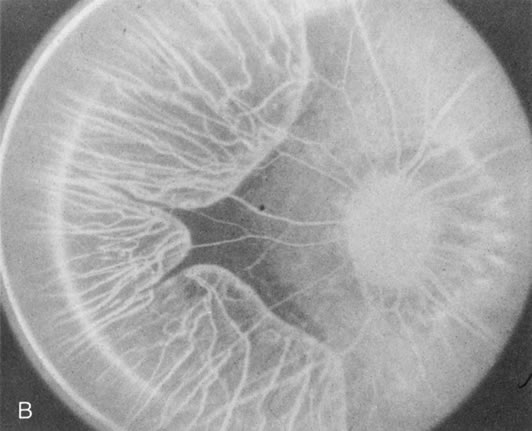

In Stargardt's disease, thes most common hereditary macular dystrophy, FA has a variety of functions. In the mildest fundus presentation, with visual symptoms and visual function out of proportion to the observed maculopathy, FA can confirm or even make the diagnosis and can avoid a mistaken diagnosis of malingering, hysteria, or central nervous system disease (Fig. 9A and B). When a maculopathy is present without surrounding parafoval flecks, FA may show patchy areas of transmission hyperfluorescence in the posterior pole, indicating a more diffuse involvement (Fig. 9C and D).

Fig. 9. Stargardt's disease–fundus flavimaculatus. The mild maculopathy (without parafoveal flecks) (A) is confirmed by the angiogram (B). The relative absence of the underlying choroidal flush, resulting in an easier visualization of the overlying retinal capillary circulation, has been referred to as the “silent” or “dark” choroid, and is considered a common finding in this disease. The diagnosis is confirmed in an individual with a pigmentary maculopathy without flecks (C). Here the angiogram demonstrates widespread transmission hyperfluorescence and a “silent” or “dark” peripapillary area (D). When the posterior pole shows multiple yellowish-white flecks (E), the angiographic findings do not necessarily correspond to the flecks (F). It should also be noted that despite the widespread abnormalities, the background choroidal fluorescence is normal.

In a large majority of patients (86% in one study),20 there is an absence or decrease in the background choroidal fluorescence (which is referred to as the “silent” or “dark” choroid) (see Fig. 9B). This warrants special attention because it occurs so frequently, is rarely found in other retinal disorders,21 and may be related to histopathology that shows an increase in lipofuscin in the RPE.22